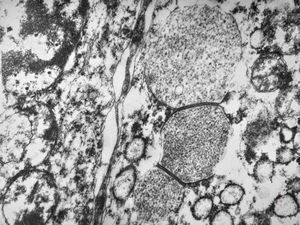

M,62y. | crystalline inclusion in endoplasmic reticulum - bone marrow, plasmocytoma